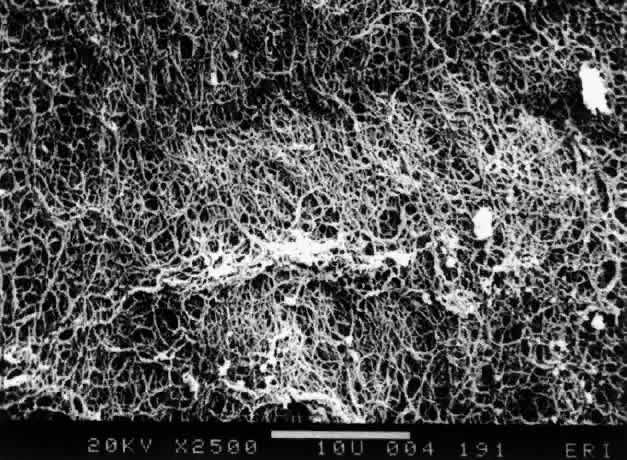

Ultrastructural studies90 have demonstrated that collagen organized in bundles of packed, parallel fibrils (Fig. 7) is the only microscopic structure that could correspond to these fibers. It has been hypothesized that the visible vitreous fibers form when HA molecules no longer separate the microscopic collagen fibrils, resulting in the aggregation of collagen fibrils into bundles from which HA molecules are excluded.82,92 Eventually the aggregates of collagen fibrils attain sufficiently large proportions that can be visualized in vitro (see Figs. 4 THROUGH 6) and clinically. The areas adjacent to these large fibers have a low density of collagen fibrils in association with HA molecules and therefore do not scatter light as intensely as the larger bundles of aggregated collagen fibrils. Furthermore, these adjacent areas offer relatively little resistance to bulk flow through vitreous, since they are largely occupied by hydrated HA.

Fig. 7. Although centrifuged to concentrate structural elements, this human vitreous specimen contains no membranes or membranous structures. Only collagen fibrils were detected. There were also bundles of parallel collagen fibrils such as the one shown here in cross section (arrow). (Sebag J: The Vitreous--Structure, Function and Pathobiology. New York, Springer-Verlag, 1989)

Fig. 12. Ultrastructure of posterior vitreous cortex in humans. Scanning electron microscopy demonstrates the dense packing of collagen fibrils in the vitreous cortex. To some extent this arrangement is exaggerated by the dehydration that occurs during specimen preparation for scanning electron microscopy (bar = 10 [a 5]mm). (Sebag J: The Vitreous--Structure, Function and Pathobiology. New York, Springer-Verlag, 1989)